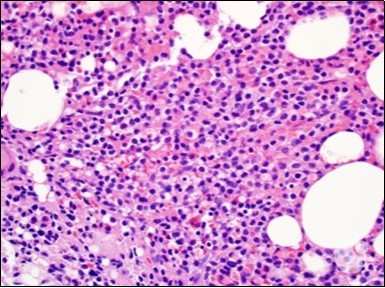

Figure 2.HCL: hairy cells with projecting cytoplasm abutting bony trabaculae(18).

The classic hairy cell is medium sized with a magnitude of 10-14µm. The moderately abundant or variable cytoplasm may be transparent or mildly basophilic. The cellular surface with the characteristic serrated perimeter depicts innumerable fragile or stout extensions of cytoplasm ,particularly discernible on the phase contrast and electron microscopy. The cytoplasm may exhibit vacuoles with occasional azurophilic granules4. The nucleus may be elliptical or reniform, folded or indented with a coarse, reticulated or a finely dispersed chromatin and inconspicuous nucleoli along with infrequent mitosis. Bone marrow aspiration or bone marrow trephine biopsy may be inadequate for diagnosis in 30%-50% individuals4. The trephine sections of the bone marrow may depict a characteristic interstitial pattern of leukaemic infiltration. Generally the bone marrow is hyper-cellular, though it may be hypo-cellular in 10-15% individuals4. The leukaemia cell ingress may be diffuse or partial, although diffuse infiltration is frequent. The partial variety of leukaemic dissemination may be ineptly categorized with an indeterminate differentiation from the uninvolved marrow. The malignant insertions may initially emerge as miniature, undefined, cellular loci. The formalin fixed, paraffin embedded sections may elucidate a crystalline zone or a “halo” appearance of the cells with a circumscribed nucleus on account of the plentiful cytoplasm4. The cellular margins may be intertwined. Fixation of bone marrow smears with Zenker’s fixative may demonstrate a retracted cytoplasm of the hairy cells with a consequent disconnected structure. The bone marrow in the absence of a malignant process may be hypo-cellular or hyper-cellular. Reticulin stains may delineate an enhanced accrual of broad, dense reticulum fibres surrounding the aggregates of leukaemia cells with the fibrous circumlocution of individual malignant cell and fibrotic extensions into the abutting, uninvolved bone marrow4.

The leukaemia cells may enunciate a characteristic immune phenotype, crucial for a confirmatory diagnosis. The peripheral blood mononuclear B cell population may display a kappa or lambda light chain restriction. The phenotype of classic hairy cell leukaemia may be delineated by concurrent, immune reactive CD19+ CD20+,CD 11c+, CD25+, CD103+ and CD123+. An intensely immune reactive CD200+ and a non reactive CD27- antigen may be present2, 4. Evaluation of a trephine bone marrow biopsy and bone marrow aspirate may define the degree of tumour infiltration. A dry tap on account of prominent bone marrow fibrosis may be elucidated at preliminary diagnosis. A decline in the normal haematopoiesis may account for a hypo-cellular marrow in 10% instances. Gradation of cellular infiltrating of the leukaemia within the bone marrow may be appropriately investigated with immune –histochemical stains2, 4. Immune staining for CD20+, annexin 1 and VE1 (a BRAF V600E stain] may validate the diagnosis and precisely analyse the extent of malignant bone marrow infiltration[8]. Determination of BRAF V600E mutation may be critical in therapeutically non responsive individuals with applicable standard therapy or in instances of multitudinous reoccurrences[9]. Deploying inhibitors of BRAF V600E gene may be efficacious in patients impervious to approved therapy. The mutation necessitates a comprehensive scrutiny of the implicated individuals with a sensitive molecular assay which may discern up to < 10% of the hairy leukaemia cells appearing in the peripheral blood smears or bone marrow aspirates diluted with peripheral blood or aspirates elucidating a dry tap[2,4]. Allele specific polymerase chain reaction (PCR) or a next generation sequencing may be optimally employed to circumvent false negative outcomes. If the leukaemia cells are sparse or if particularly sensitive & efficacious molecular techniques are not accessible, the application of appropriate immune histochemical stains to the bone marrow biopsy such as a BRAF V600E mutation stain (VE1) may detect the hairy cells and conclusively diagnose the condition[2,4,10]. Figure 1, Figure 2, Figure 3, Figure 4, Figure 5, Figure 6, Figure 7, Figure 8, Figure 9, Figure 10, Figure 11, Figure 12, Figure 13, Figure 14.